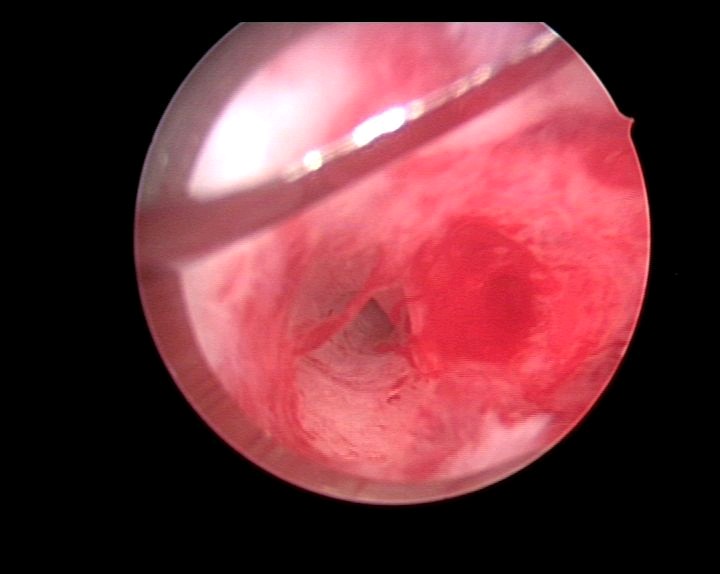

患者29岁,G1P0,人流术后闭经半年,2015年宫腔镜探查,发现宫颈管粘连,宫腔两侧粘连,冷刀(钩型刀)切割粘连,恢复宫腔形态,显露双侧输卵管开口。术后偶尔监测排卵试孕2年未孕,又过了1年,2018年不经意间自然妊娠,足月分娩。现40岁,G2P1。